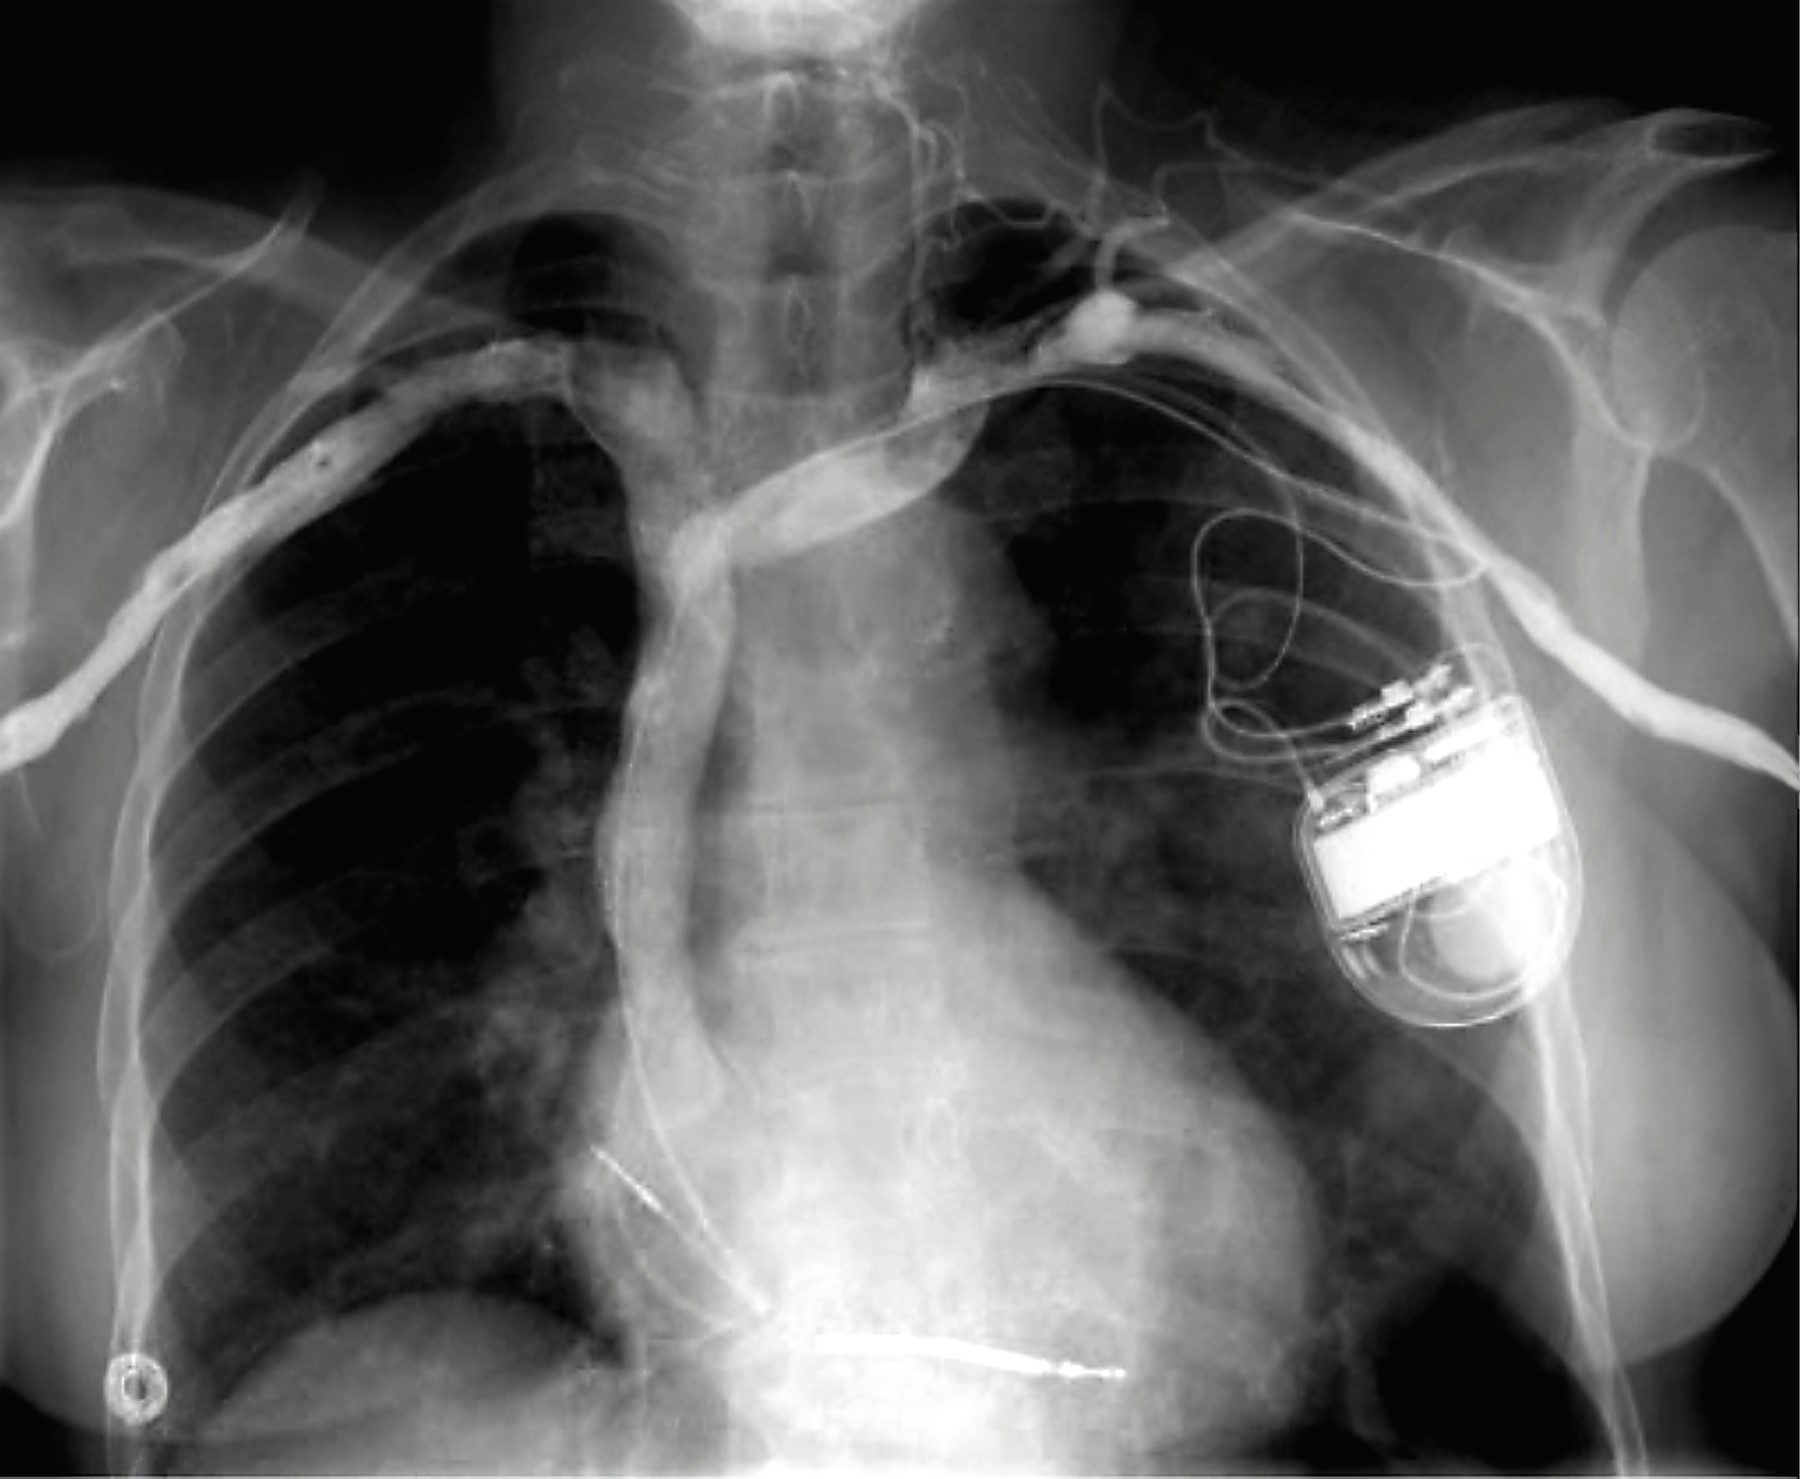

Romunijo pretresa kazenska preiskava, v katero se je ujelo pet zdravnikov. Skupina je osumljena nezakonite ponovne uporabe medicinskih vsadkov, kot so srčni spodbujevalniki. Te naj bi vzeli iz trupel mrtvih pacientov in jih na podlagi lažnih diagnoz ter pogosto brez potrebe ponovno vsadili v žive bolnike. Večinoma je bil izvor ponovno uporabljenih vsadkov tudi neznan.

V Romuniji poteka odmevna kazenska preiskava, ki je dosegla tudi mednarodno javnost. Vanjo se je za zdaj ujelo pet zdravnikov, ki so osumljeni nezakonite ponovne uporabe že uporabljenih medicinskih vsadkov, kot so denimo srčni spodbujevalniki. Te naj bi vzeli iz trupel pacientov in jih ponovno vstavili v žive bolnike, poroča Guardian.

Zdravnik naj bi nezakonite vsadke od leta 2017 uporabil v skupno 238 posegih. Pogosto je bil izvor ponovno uporabljenih vsadkov tudi neznan. Pridržani zdravnik je svoje paciente tako izpostavljal resnim zapletom in smrti, navaja Guardian.

"Velik del vsadkov, ki jih je priporočil zdravnik … sploh ni bil potreben," so tožilci zapisali v izjavi. Zdravnik naj bi medicinske pripomočke vstavljal na podlagi lažnih diagnoz oziroma predhodno predpisanih zdravil, ki so po uporabi sprožila specifične simptome.